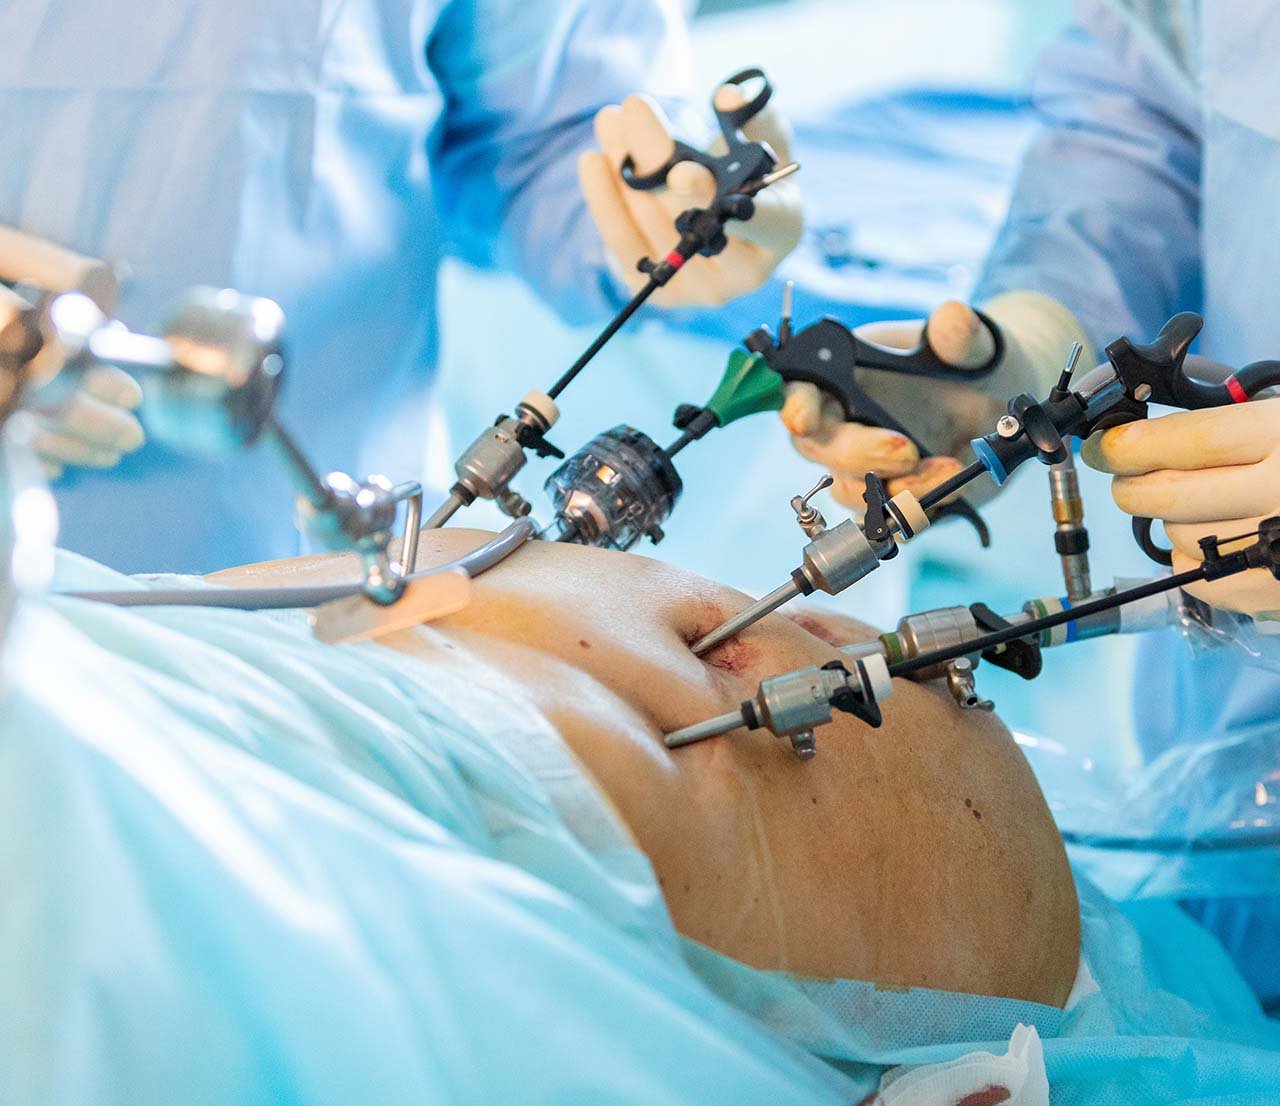

We offer advanced laparoscopic procedures for faster recovery and minimal pain. Expert surgeons handle hernia, liver, gall bladder, and appendix surgeries with precision. Modern equipment ensures safe and effective treatment outcomes. Suitable for patients seeking minimally invasive options.